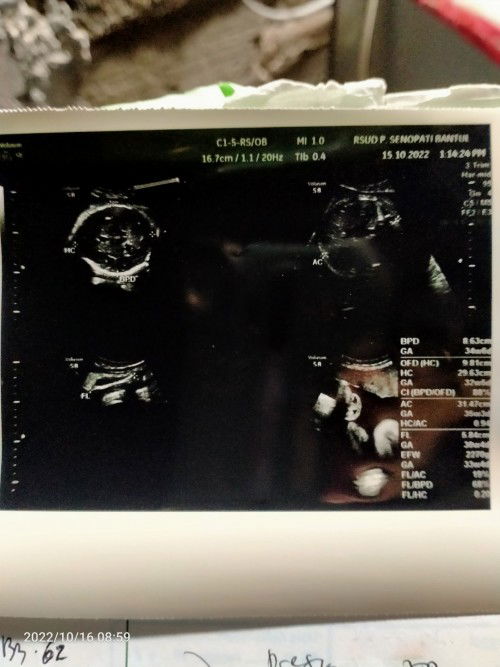

Bun, adakah yg mengalami hal seperti saya? UK 30w bbj >2kg. Dokter bilang kemarin kalo bayinya besar & cairan ketuban banyak, sehingga penuh yg menimbulkan perut sering kencang². Kata dokter efek dari gula yg tak terkontrol. Padahal saya sendiri jarang konsumsi manis semenjak sbelum hamil. Pas dikasih tau gitu, rasanya kaget banget, pengen nangis tpi ga bisa. Karno posisi bayinya udah dibawah banget, jadi maaf tulang kemaluan udah nyeri², buat jalan udah agak sulit. Pikirannya jdi kemana-mana. Ini foto usg kemarin pas kontrol. Besok senin dijadwalkan periksa ke poli dalam bun. Minta do'anya bun, agar saya & debay diberikan kesehatan 🤲